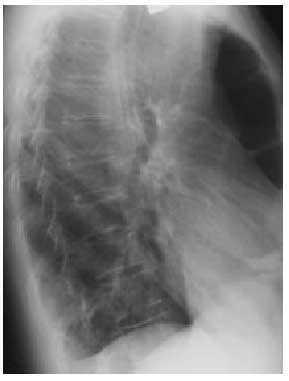

En la radiografía de tórax no se observó condensación de campos pulmonares, presentando en la proyección posteroanterior, en el borde cardíaco derecho, una imagen hidroaérea en la que se aprecian haustras, todo ello compatible con el intestino grueso (figs. 1 y 2).

Fig. 1. Imagen radiológica en posteroanterior de tórax.

Presentamos la imagen radiológica de un enfisema mediastínico, o neumomediastino si nos atenemos a su definición (presencia de aire en el mediastino), que en una rápida valoración puede resultar desconcertante, y que una completa anamnesis resuelve cualquier duda. El neumomediastino es una entidad muy poco frecuente; suele ser secundario a traumatismos, maniobras iatrogénicas y de tipo espontáneo, cuando no se haya una causa desencadenante evidente, siendo el 25% de los casos de tipo idiopático.

El diagnóstico es fundamentalmente radiológico en el tórax, en las imágenes posteroranterior y lateral, pues en ellas se aprecia mejor el aire mediastínico. Hamma insiste en el hecho de que radiológicamente pueden estar asociados neumotórax espontáneo y de mediastino, por lo que la búsqueda del enfisema mediastínico debe ser sistemática, especialmente en los izquierdos. Otro signo radiológico importante es el hallazgo de aire en los músculos cervicales, por lo que realizar una radiografía de cuello será imprescindible en todo caso sospechoso de enfisema mediastínico agudo, así como en los traumatismos torácicos que cursen con neumotórax.